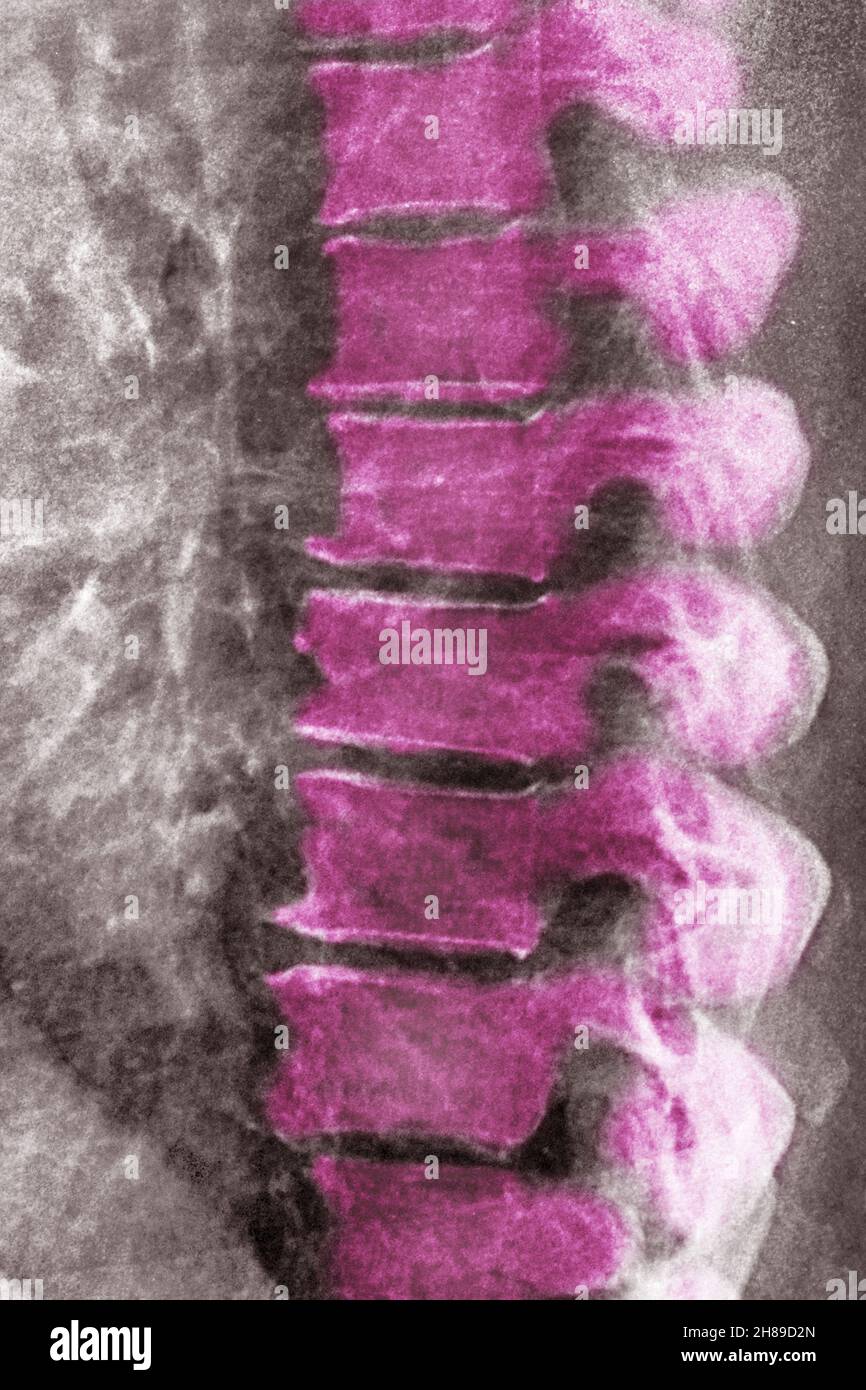

Lumbar degenerative disc disease Stock Photo Alamy Lumbar Disc Disease Examples lumbar disk disease may occur when a disk in the low back area of the spine bulges or herniates from between the bony area of the spine. lumbar degenerative disk disease. Your lower back, or lumbar spine, has five vertebrae, which are the largest. outline the components of proper evaluation and assessment of a patient presenting with. Lumbar Disc Disease Examples.

Lumbar degenerative disc disease Stock Photo Alamy Lumbar Disc Disease Examples outline the components of proper evaluation and assessment of a patient presenting with lumbar degenerative disc disease, including any. the region in your neck area is the cervical spine, the region in your chest is the thoracic spine and the region in your low back is the lumbar spine. Your lower back, or lumbar spine, has five vertebrae,. Lumbar Disc Disease Examples.